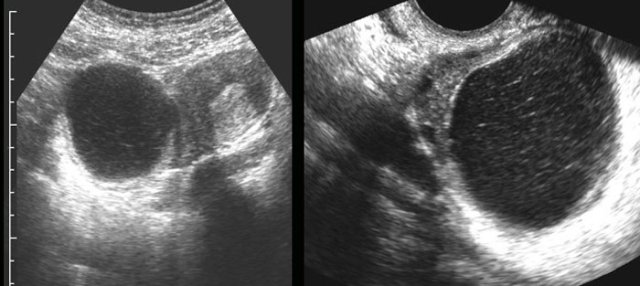

case 1

This pregnant

patient presented with acute LLQ pain.

US revealed an intact pregnancy of 8 weeks

and left of the uterus a painful, non-compressible (arrowheads), partly cystic,

partly solid mass, suspect for adnexal torsion.

At

laparoscopy a 360 degrees torsion of a luteal cyst was found.

After detorsion

the liquid component was aspirated.

case 2

A 21-week pregnant woman was submitted with suspected appendicitis. She had similar attacks before.

US shows an intact pregnancy and in the right lower quadrant a large dermoid cyst (arrowheads).

laparotomy the dermoid cyst was oedematous, probably due to intermittent torsion.

Ovary-sparing resection was successful.